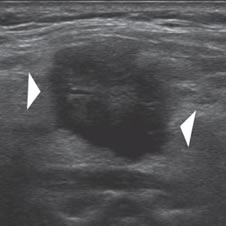

Un nódulo que tiene un componente quístico significativo, usualmente es un nódulo benigno hiperplástico, que ha acumulado abundante coloide (Figura 2a) o bien, un nódulo sólido que ha experimentado un proceso de degeneración colicuativa o hemorragia (Figura 2b). El coloide o el contenido líquido de un nódulo se ve anecogénico (negro en la imagen ecográfica) y las estructuras sólidas se ven ecogénicas (distintos tonos de grises), siendo la ecogenicidad similar al del parénquima tiroideo. En un nódulo sólido la ecoestructura y la ecogenicidad pueden ser variables. En general, la frecuencia de carcinoma es muy baja en nódulos quísticos13 y la mayoría de los carcinomas se presentan como nódulos sólidos (Figura 2c).

Figura 2. a) Quiste coloideo anecogénico y focos ecogénicos (flecha) con artefacto en cola de cometa; b) Nódulo mixto sólido-quístico (cabezas de flechas). Imagen vegetante (flecha) adherida a un tabique que se proyecta al lumen; c) Comparación entre el aspecto ecográfico de un cáncer papilar sólido (flecha abierta) y un quiste coloideo anecogénico.